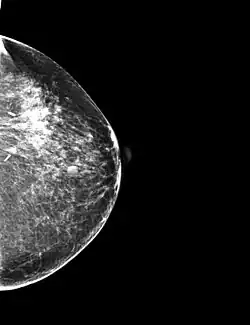

Se trata de la mejora de la imagen considerando los métodos de procesamiento que se basan solo en la intensidad de píxeles individuales. En lo que sigue llamaremos r y s a la intensidad de los píxeles antes y después del procesado. A continuación se presentan ejemplos de tratamiento de imagen por procesamiento de punto utilizando el software de acceso libre ImageJ:

-Negativos de imágenes: La idea de esta transformación es invertir el orden de blanco a negro, de forma que la intensidad de la imagen de salida disminuya conforme la intensidad de la imagen de entrada aumente. Mediante ImageJ es sencillo realizar el negativo de una imagen. Esta se conseguiría a partir de la lookup table, Invert LUT.